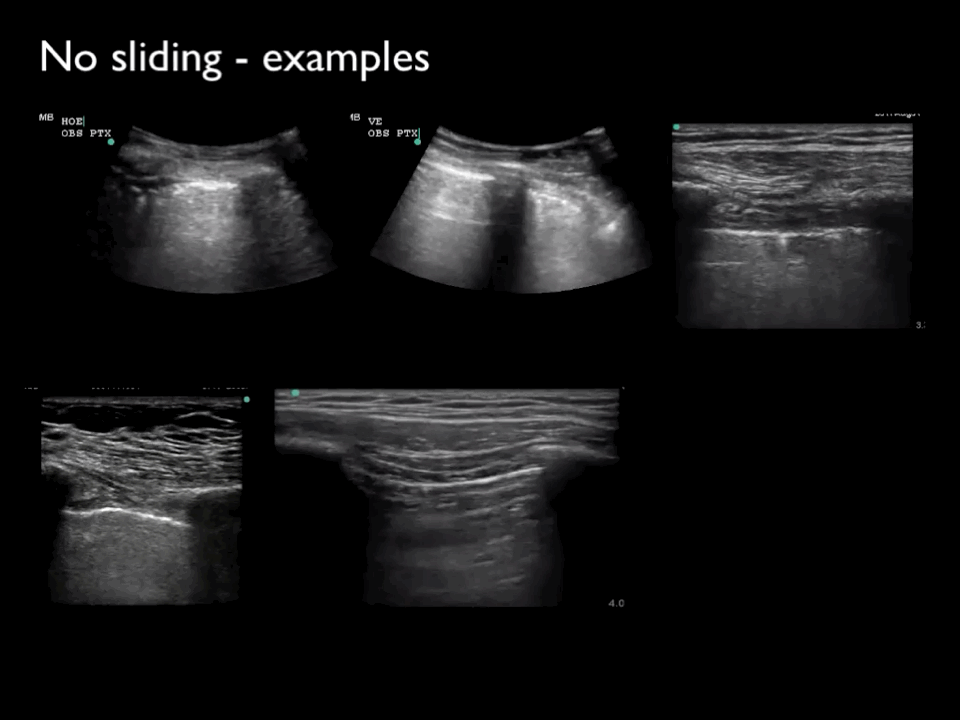

Five different clips showing the absence of lung sliding, lung pulse, and B-lines, indicating suspicion of pneumothorax.